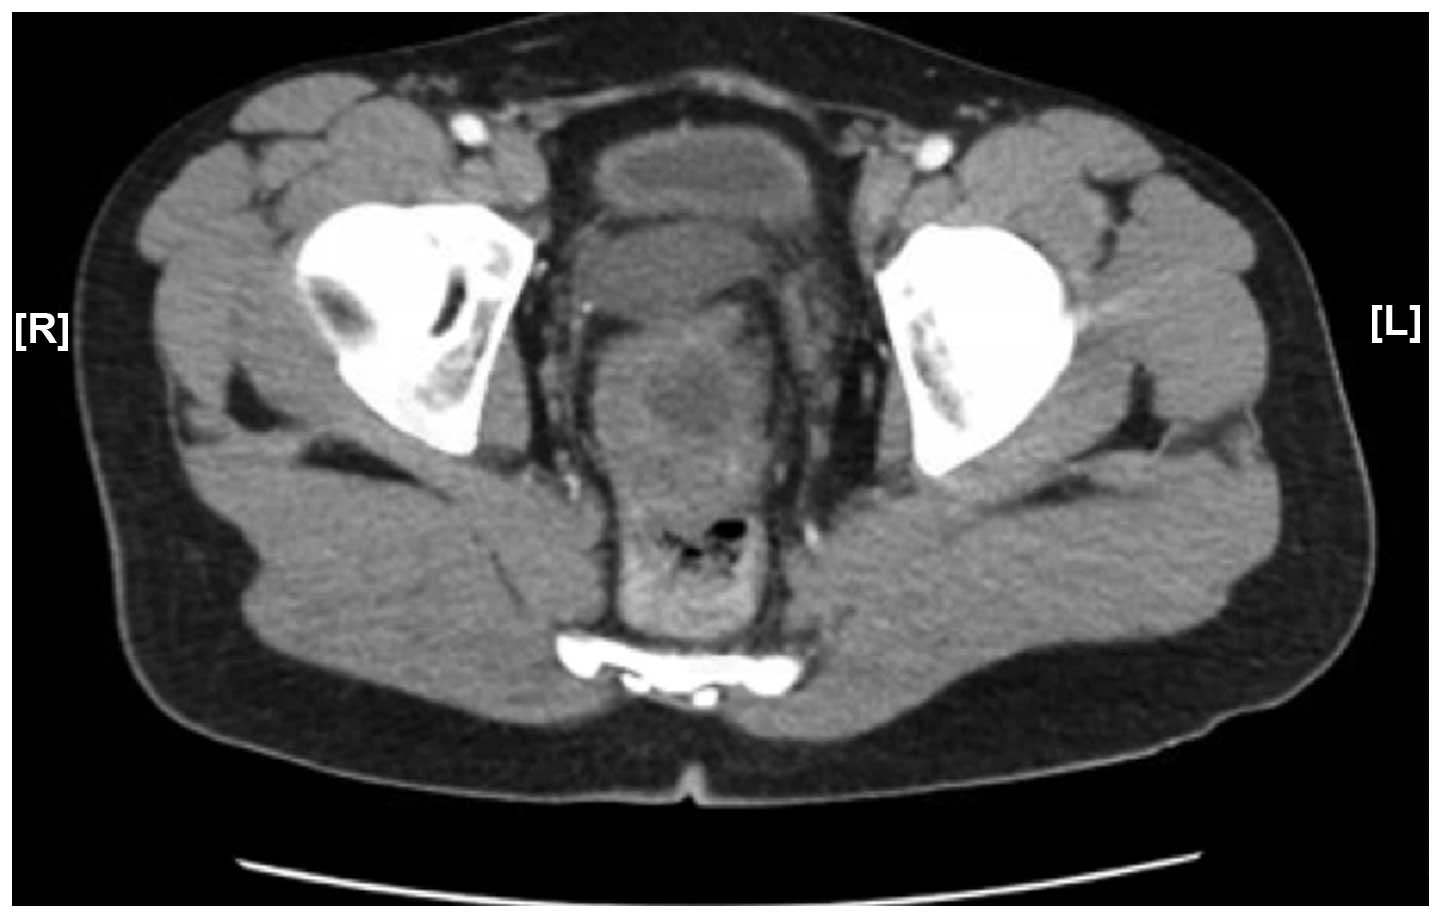

In August 2014, a 27-year-old Hispanic male patient presented to the Emergency Department of Raritan Bay Medical Center (Perth Amboy, NJ, USA) with the complaint of novel onset gross painless hematuria following a 4-month history of generalized abdominal pain. The patient's history revealed that he was born in Peru, is a non-smoker, drinks socially, and the only relevant family history is that his father had colon cancer. The patient stated he has been working at UPS for only a few years and his job requires him to load trucks, however the patient was unaware of any chemical exposure. The patient underwent computed tomography (CT) scan on the abdomen and pelvis without contrast which revealed a partially calcified mass at the dome of the urinary bladder with infiltration of the adjacent lower abdominal mesentery. The patient then underwent a multiphasic post-contrast CT scan of the abdomen/pelvis (Fig. 1) which also demonstrated a coarsely calcified mass at the dome of urinary bladder with reticulation of the mesenteric fat with nodular mesenteric implants indicating peritoneal carcinomatosis. Following diagnosis, cystoscopy with transurethral resection of bladder tumor was performed with insertion of a right ureteral stent and bladder biopsies were taken. However, complete resection of the tumor was not possible due to the extensive nature of the tumor. Following dome-biopsy, a diagnosis was made of urachal primary mucinous adenocarcinoma with prominent signet ring features and extension into the subepithelial connective tissues. The tumor was staged at pT1, according to the modified International Union for Cancer Control staging criteria (2), but a higher stage could not be established from the sample biopsied at the time. Immunohistochemical analysis revealed that the tumor cells were strongly positive for CK20 and CDX2 and negative for p53, CK7, keratin 903, thrombomodulin, and p63. Post resection, the patient remains alive and responded well to a 6-week course of Bacillus Calmette-Guerin intravesical chemotherapy administered in October 2014 at the Rutgers Cancer Institute of New Jersey (New Brunswick, NJ, USA).